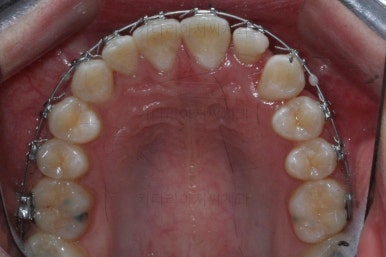

왜소치 좌우로 틈을 일부러 만든 상태입니다.

그 후에 임시 개념으로 사이즈를 크게 만들어 줬어요.

사이즈를 크게 한 뒤에도 약간의 틈이 남아서 다시 틈을 줄여주는 과정을 진행했어요.

아무래도 치아 크기의 문제가 있다보니 완벽한 교합을 맞추기는 힘들었짐나 가능한 마무리를 더 해보기로 했어요.

마무리 때의 모습입니다.